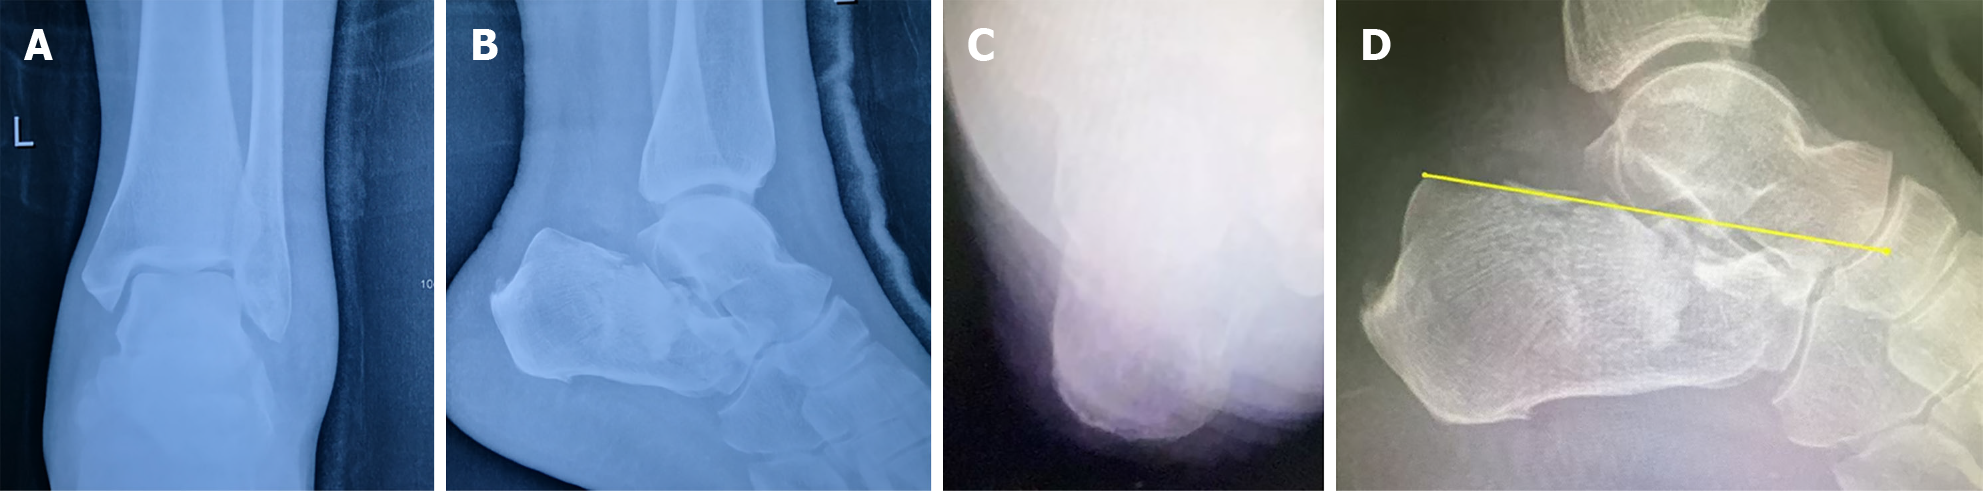

Figure 6 Böhler angle changes after screws removal.

After 7 months postoperatively, screws were removed and radiography assessments were carried out in follow-up. A and B: Böhler angle was at 22° at 7 months; C and D: Despite requiring surgical intervention for an ankle fracture due to trauma, at 39 months postoperatively the calcaneal Böhler angle was preserved at the initial 22° reduction.